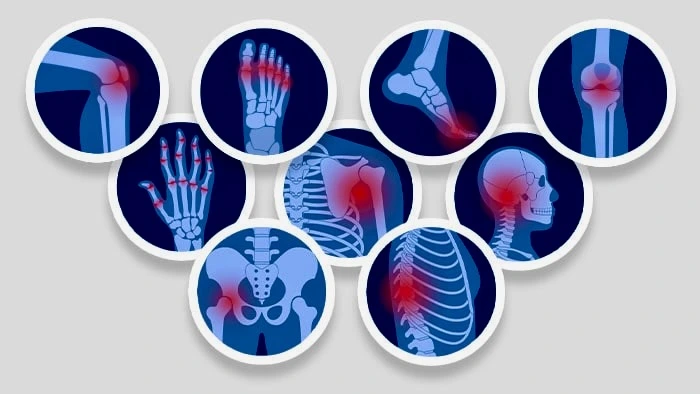

A Pain Management Doctor in Jaipur can really help when the pain that happens every day starts to tinge every aspect of life – sleep, moods, energy, movement, and confidence are all affected. People tend to go on relying on pain-relieving medication, topical creams, or continued physiotherapist sessions with the expectation that the pain will just fade away, but if that persists or keeps recurring, it’s likely that it’s time to go deeper and come up with a strategy. That’s where a Pain Management Specialist or Pain Management Doctor in Jaipur steps in. The strategy here is meant to locate the root cause of the pain and then eliminate it while also bringing back function instead of mere relief. If you are looking to find yourself a Pain Management Doctor in Jaipur or a Pain Relief Doctor in Jaipur, you are likely looking to access a specialist who can provide you with more modern alternatives, especially when the current ones are not delivering well, or when the pain caused is interfering with daily life or looking for alternatives to surgeries. The current treatment for pain involves very modern approaches like image-guided injections, nerve blocks, and pain recovery plans. Even Dr. Rakesh Kumar Kumawat has been adjudged as one of the most reliable Pain Relief Doctors in Jaipur, as he has expert skills in performing minimally invasive procedures along with proper knowledge of how to tackle pain.

Common Cases Handled by a Pain Relief Specialist

Citizens require a Pain Relief Doctor in Jaipur due to reasons such as:

Knee Pain and Osteoarthritis

Joint pain can become chronic due to wear, inflammation, and degeneration. Some patients can benefit from Advanced, Non-Surgical therapies such as the Genicular Nerve Block procedure for relieving pain.

Back Pain and Sciatica

“Lower back pain may result from problems with discs, pinched nerves, irritated facet joints, or muscle imbalances. ‘Sciatica’ can refer to a sharp pain shooting down the leg.” – Dr. Andrew Weil Neck pain,

shoulder pain, or any pangs in the arm with a tingling sensation can indicate irritated nerves or inflamed joints. When simple care is not sufficient, specific remedies will assist with alleviating this pain.

Nerve pain, or neuropathy,

Joint pain and pain from inflammation are steadily eroding functional movement and quality-of-life activities. A specific plan of action can make a difference in management. The treatment is always case-specific. A specialist’s care is focused around a safe diagnosis and a practical, tailored approach, rather than best-all-around general pain relief. The kinds of patients seeking a Pain Relief Doctor, a Pain Management Doctor, or a specialist Pain Management Specialist in Jaipur include those dealing with knee pain, like arthritis, back and sciatica pain, neck pain, cervical spondylosis, general joint pain, and nerve pain. A number also seek a specialist for specifically wrist pain, such as Carpal Tunnel Syndrome, where the patient can experience tingling, numbness, along with weakness in the hands, affecting their work. For the upper body range of motion, pain management may be necessary for shoulder problems, such as Frozen Shoulder, Adhesive Capsulitis, accompanied by limited flexibility, and elbow pain, such as Tennis Elbow, associated with gripping, lifting, and repeated use of the hands.